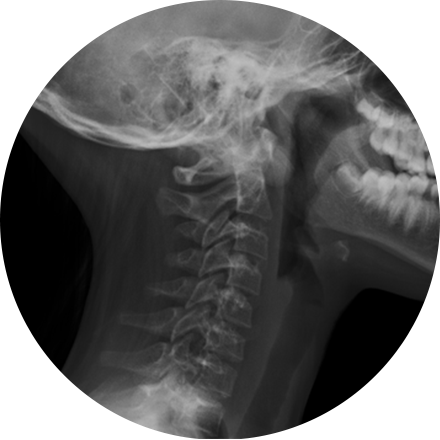

During the procedure, electromagnetic radiation passes through the body onto “film” (now digitized and displayed on a computer screen). Dense structures such as bone absorb most of the radiation and appear white on the digital image. Structures that are less dense like air appear black. Everything in between appears a different shade of gray.

Digital X-rays are used to diagnose a wide range of illnesses and injuries, including musculoskeletal injuries, cancer, blocked arteries, abdominal pain, sinus disease, spinal problems and other abnormalities.